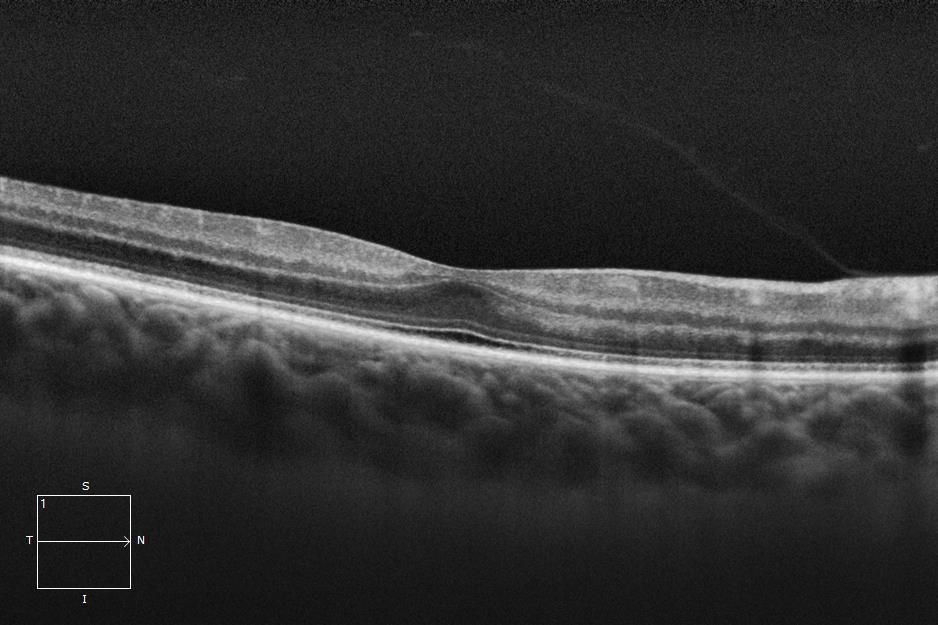

Three different patients with isolated grade 1 foveal hypoplasia. The definitions of fovea plana and foveal hypoplasia have led to controversy among experts. The term fovea plane refers to the anatomical absence of a foveal pit. An estimated 3% of children with clinically normal eyes have an underdeveloped foveal pit on OCT. According to some experts, a foveal pit is not absolutely necessary for foveal cone specialization. A diagnosis of fovea plana alone does not automatically herald functional disability. It is possible to maintain adequate visual acuity in an eye with a fovea plana. Foveal hypoplasia refers to an underdeveloped fovea with vision loss. Foveal hypoplasia has also been seen in conditions such as aniridia, albinism, achromatopsia, nanophthalmus, and incontinence. pigment and premature retinopathy.

In contrast to other definitions, Thomas et al. defined foveal hypoplasia as the persistence of inner retinal layers in the fovea and developed a grading system based on optical coherence tomography features. According to this grading system, grades 2, 3, and 4 of foveal hypoplasia corresponded to the fovea plana.

Grade 3 foveal hypoplasia represents all the features of grade 2 except that there is no lengthening of the OS segment.